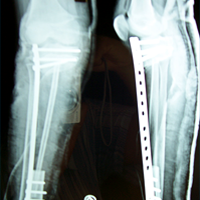

Case:5 Ewing sarcoma with implant failure

Orthopedic Oncology Doctor In Ahmedabad

Breakage of Nail

Sports Injuries Doctor

Refixation with Angle Bladed Plate and Sever Graft

Spine Best doctor

Ewing's Post Nailing and Bone Grafting

Best Trauma Surgeon in Ahmedbad

3 Months Post -Op

Joint Replacement

6 Months Post-Op